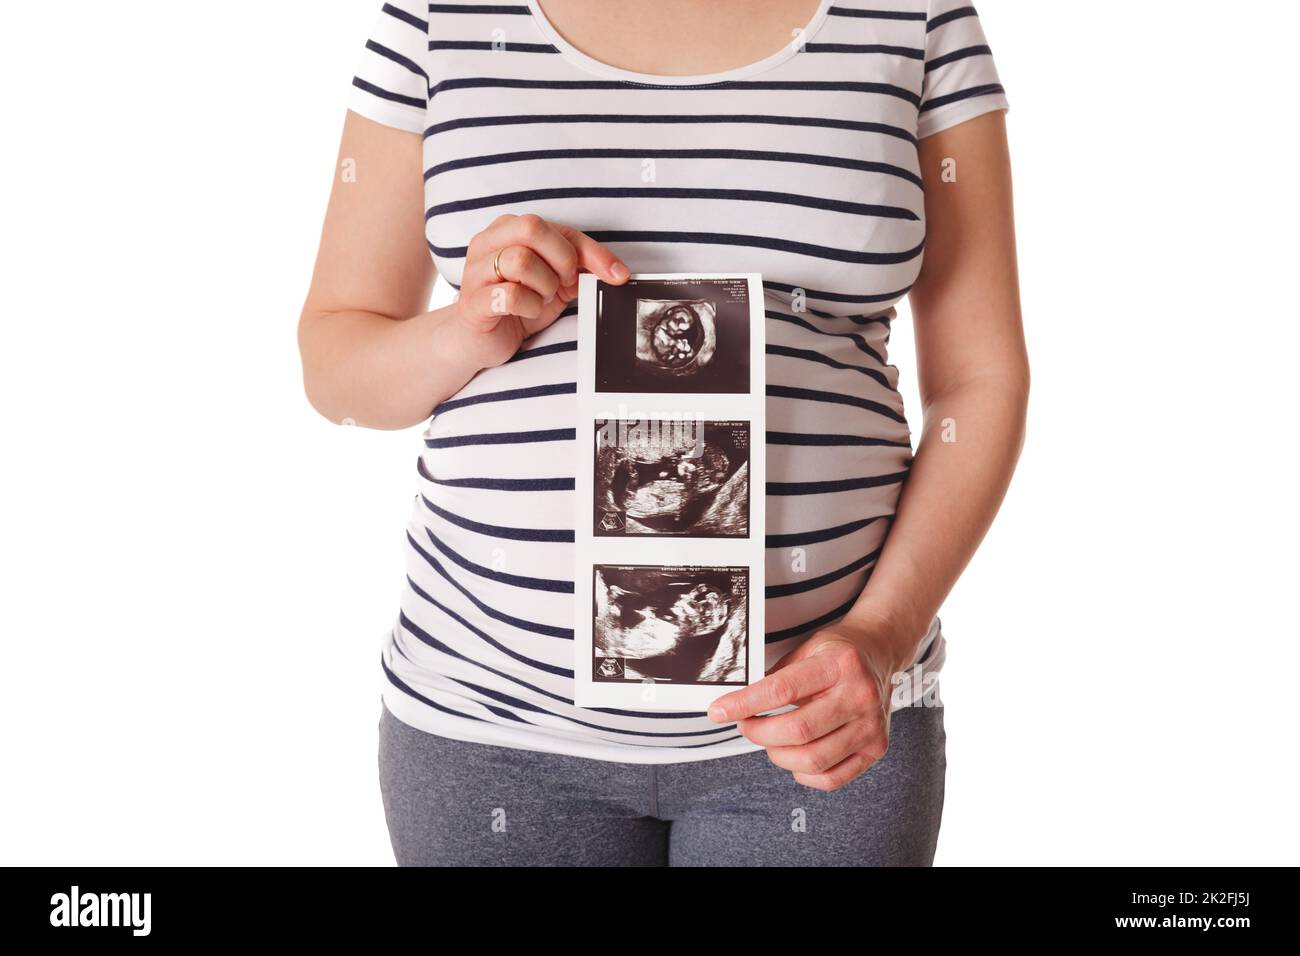

Donna incinta in piedi e tenendo la sua scansione del bambino a ultrasuoni Foto Stockhttps://www.alamy.it/image-license-details/?v=1https://www.alamy.it/donna-incinta-in-piedi-e-tenendo-la-sua-scansione-del-bambino-a-ultrasuoni-image483463166.html

Donna incinta in piedi e tenendo la sua scansione del bambino a ultrasuoni Foto Stockhttps://www.alamy.it/image-license-details/?v=1https://www.alamy.it/donna-incinta-in-piedi-e-tenendo-la-sua-scansione-del-bambino-a-ultrasuoni-image483463166.htmlRF2K2FJ5J–Donna incinta in piedi e tenendo la sua scansione del bambino a ultrasuoni